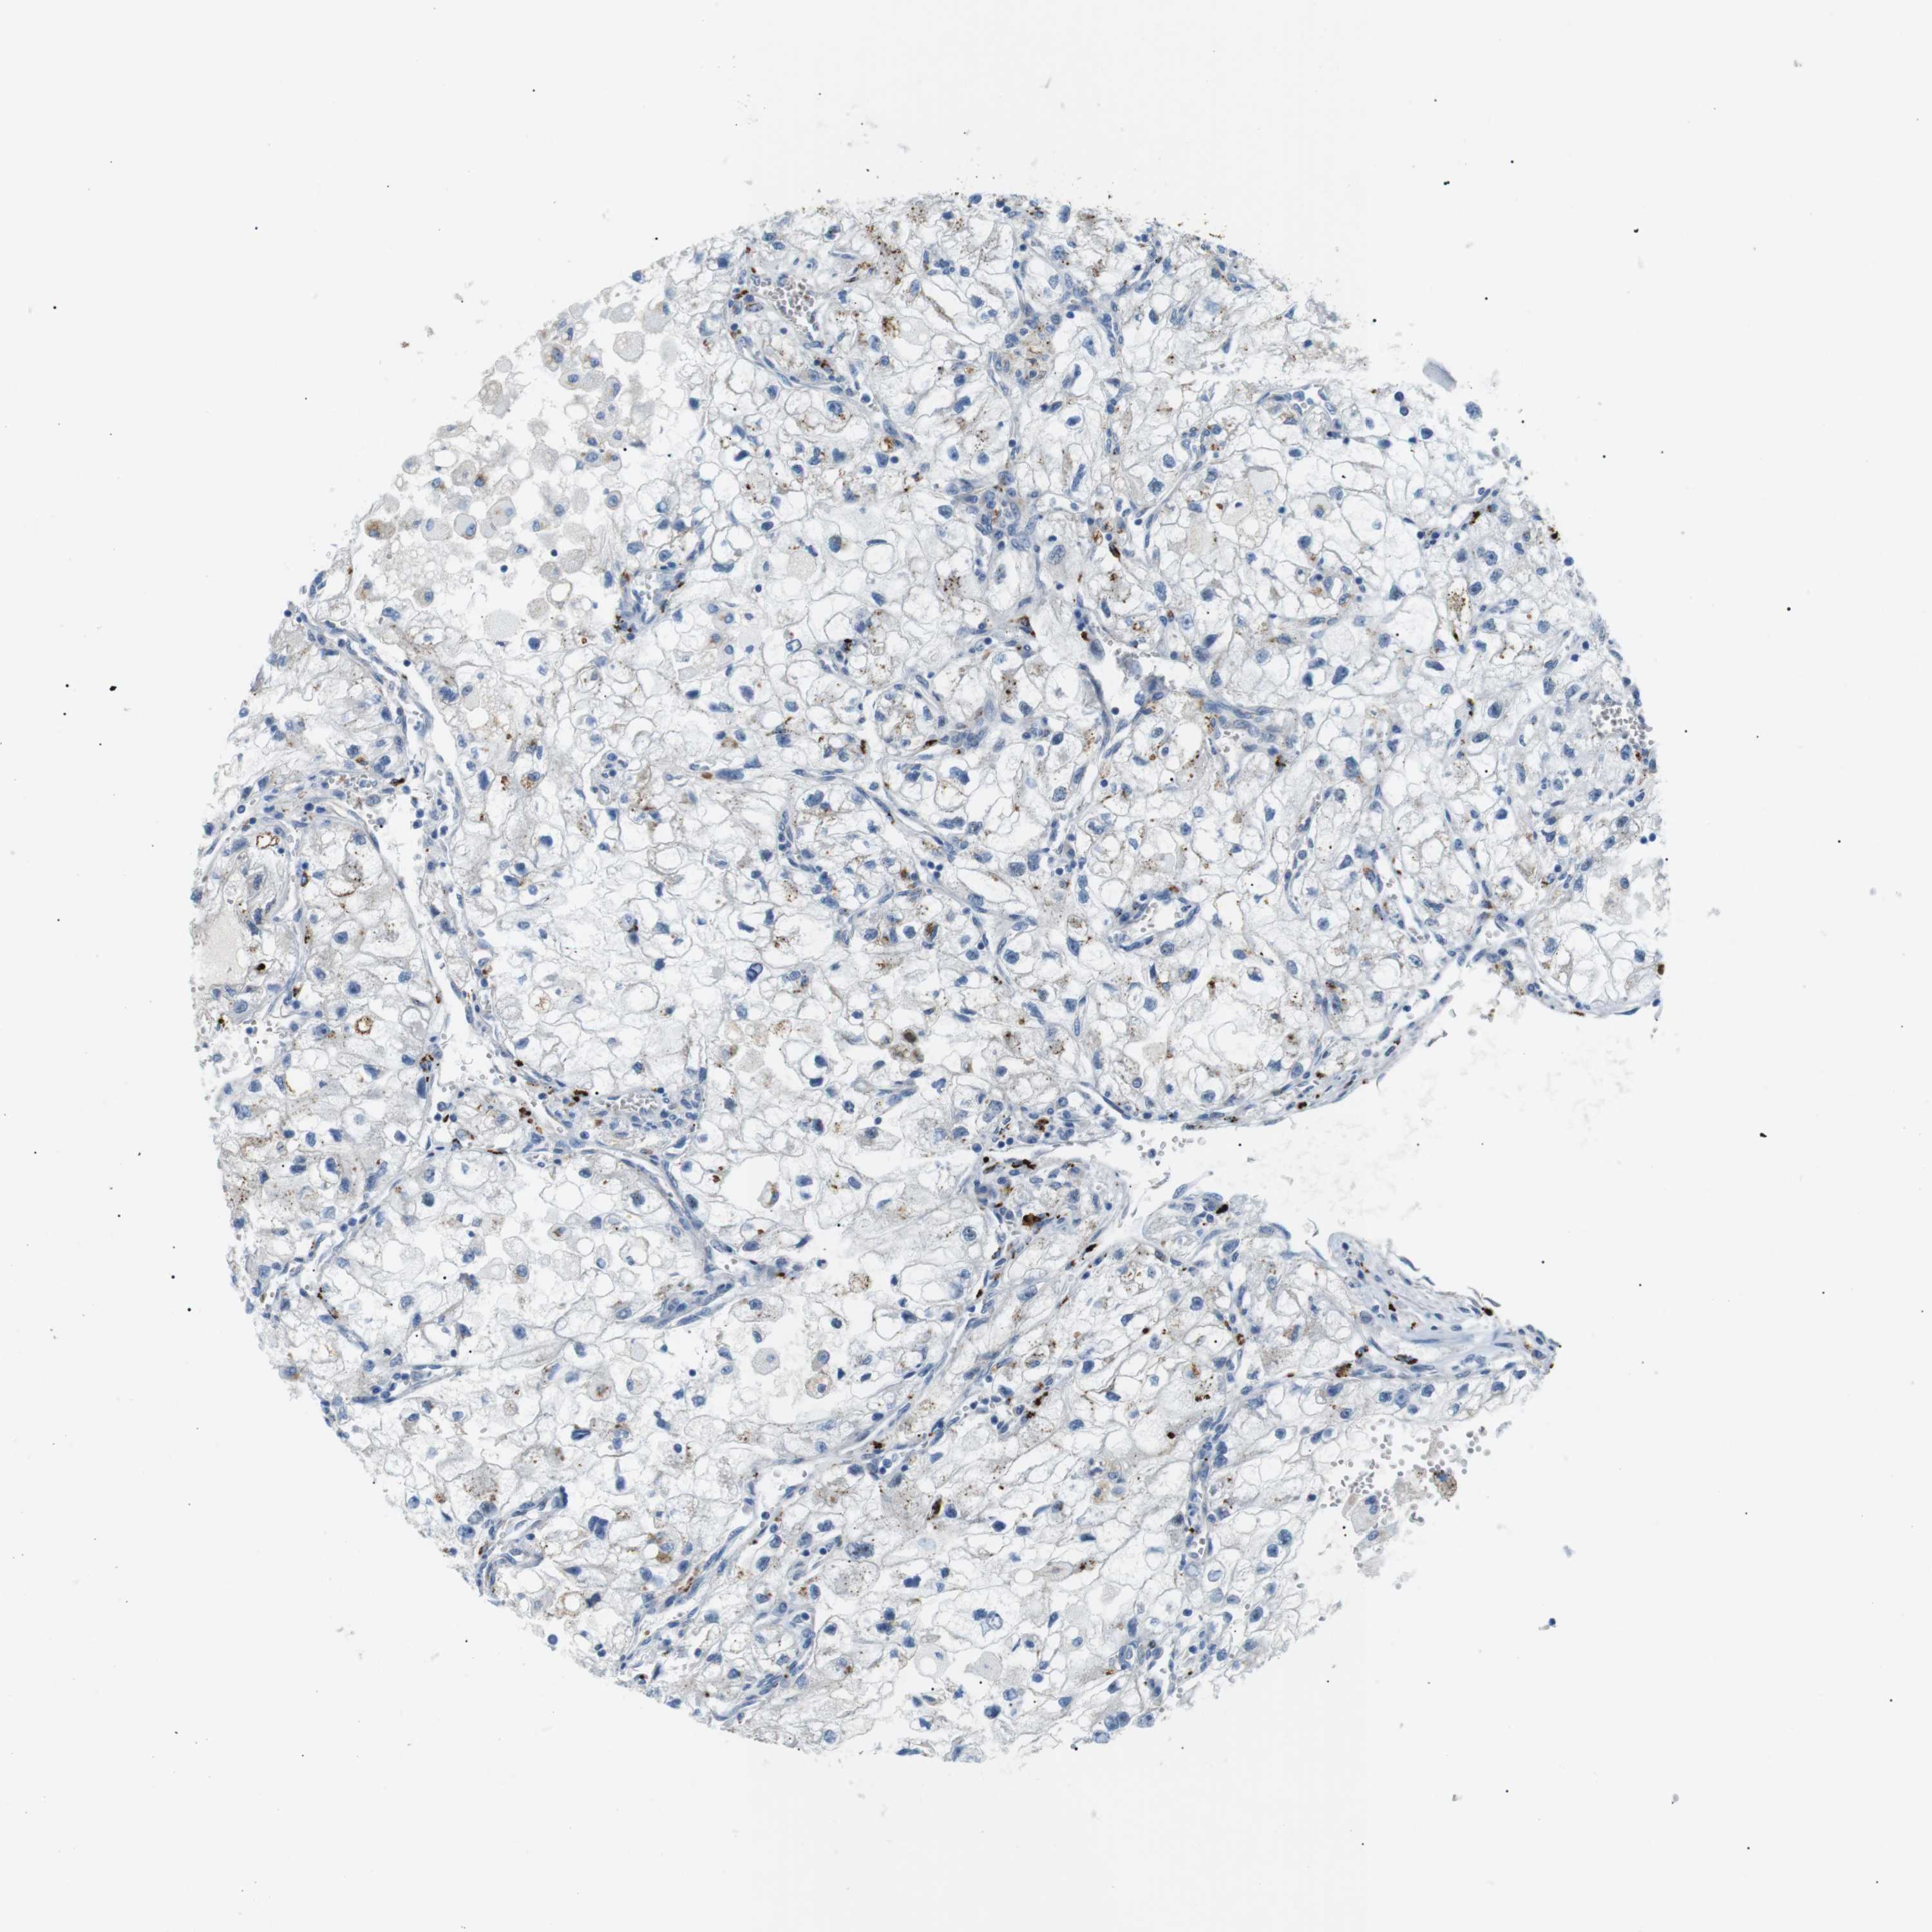

KIDNEY RENAL CLEAR CELL CARCINOMA (VALIDATION) - Interactive survival scatter ploti

The Survival Scatter plot shows the clinical status (i.e. dead or alive) for all individuals in the patient cohort, based on the same data that underlies the corresponding Kaplan-Meier plots. Patients that are alive at last time for follow-up are shown in blue and patients who have died during the study are shown in red.

The x-axis shows the expression levels (FPKM) of the investigated gene in the tumor tissue at the time of diagnosis. The y-axis shows the follow-up time after diagnosis (years). Both axes are complimented with kernel density curves demonstrating the data density over the axes. The top density plot shows the expression levels (FPKM) distribution among dead (red) and alive patients (blue). The right density plot shows the data density of the survived years of dead patients with high and low expression levels respectively, stratified using the cutoff indicated by the vertical dashed line through the Survival Scatter plot. This cutoff is automatically defined based on the FPKM cutoff that minimizes the p-score. The cutoff can be changed by dragging the vertical line or by entering a cutoff value in the square labeled "Current cut-off".

Under the Survival Scatter plot the p-score landscape (black curve; left axis) is shown together with dead median separation (red curve; right axis). Dead median separation is the difference in median mRNA expression between patients who have died with high and low expression, respectively. It is calculated as follows: median FPKM expression of dead patients with high expression - median FPKM expression of dead patients with low expression. This is intended to aid the user in visually exploring custom cutoffs and the associated p-scores and dead median separation.

Individual patient data is displayed and can be filtered by clicking on one or more of the category buttons on the top of the page. Categories describing expression level and patient information include: high, low, alive, dead, female, male and tumor stages. The scale of the x-axis can be toggled between linear and log-scale by clicking on the "x log" button. Mouse-over function shows TCGA ID, patient information and mRNA expression (FPKM) for each patient.

& Survival analysisi

Kaplan-Meier plots summarize results from analysis of correlation between mRNA expression level and patient survival. Patients were divided based on level of expression into one of the two groups "low" (under cut off) or "high" (over cut off). X-axis shows time for survival (years) and y-axis shows the probability of survival, where 1.0 corresponds to 100 percent.

B4GALNT2 is not prognostic in Kidney Renal Clear Cell Carcinoma (validation)

Best expression cut offi

Based on the FPKM value of each gene, patients were classified into two groups and association between prognosis (survival) and gene expression (FPKM) was examined. The best expression cut-off refers the FPKM value that yields maximal difference with regard to survival between the two groups at the lowest log-rank P-value. Best expression cut-off was selected based on survival analysis .

When clicking on this number, the vertical dashed line indicating cut-off, the interactive survival plot, and the Kaplan-Meier curve will be adjusted to show results based on the best expression cut-off.

: 4.43

P scorei

Log-rank P value for Kaplan-Meier plot showing results from analysis of correlation between mRNA expression level and patient survival.

N/A

TCGA RNA samplesi

RNA-seq data is reported as average FPKM (number Fragments Per Kilobase of exon per Million reads), generated by the The Cancer Genome Atlas (TCGA) .

Normal distribution across the dataset is visualized with box plots, shown as median and 25th and 75th percentiles. Points are displayed as outliers if they are above or below 1.5 times the interquartile range. FPKM values of the individual samples are presented next to the box plot.

Average pTPM 5.8

Number of samples 100